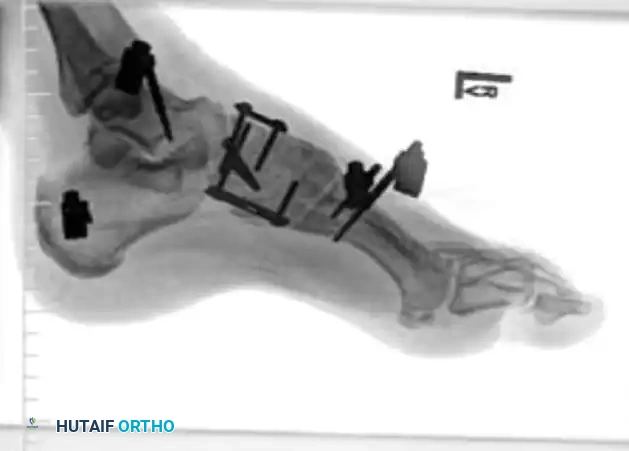

3. Fixation:

* The "Home Run Screw": A 3.5-mm or 4.0-mm solid cortical screw is placed from the medial cuneiform into the base of the second metatarsal, replicating the vector of the Lisfranc ligament.

* The 1st, 2nd, and 3rd TMT joints are typically rigidly fixed with transarticular screws or dorsal bridge plates.

* The 4th and 5th TMT joints are highly mobile. If unstable, they should be fixed with smooth Kirschner wires (K-wires) rather than rigid screws to preserve their essential sagittal plane motion. K-wires are typically removed at 6 weeks.